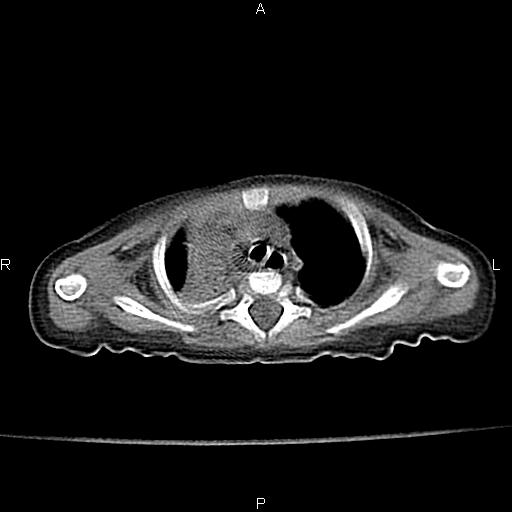

以下是引用jsdtd在2010-7-26 14:42:00的发言:[br]胸腺呈帆状,体位所致,没事。

以下是引用aa13877358820在2010-7-26 12:35:00的发言:[br]男性,三个月,卧位胸片,咳嗽、气促、发热14天,两肺闻及细小水泡音。[br]